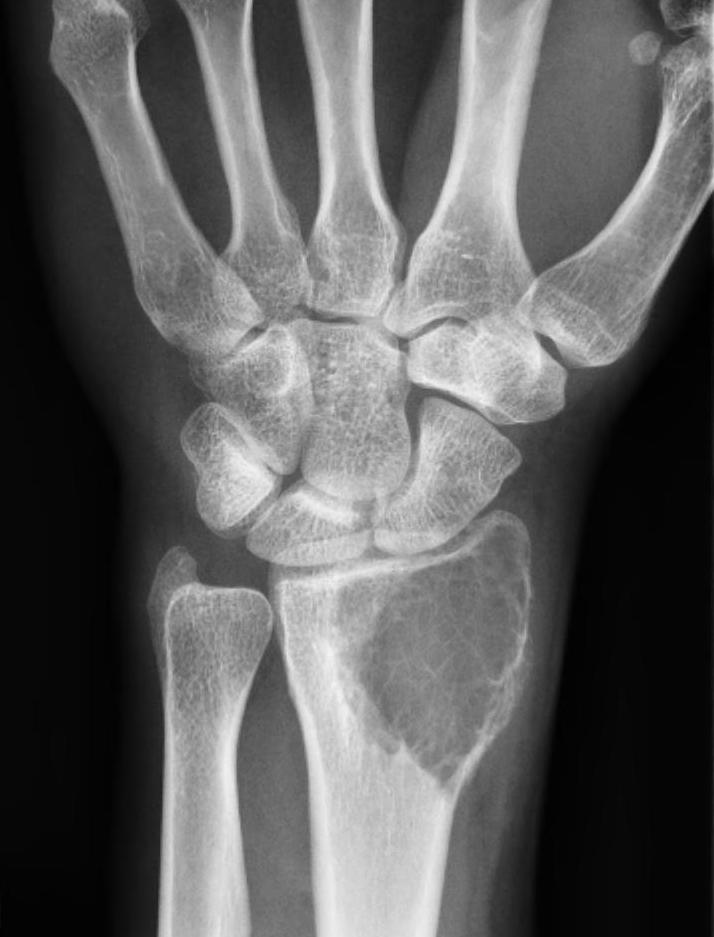

Distal Radius

Abuhejleh et al Eur J Orthop Traumatol Surg 2020

- 57 patients with GCT's of distal radius

- 29% (10/34) recurrence with intra-lesional treatement but no complications

- 4% (1/23) recurrence with wide resection / arthrodesis but 30% complication rate

- increased risk recurrence for Grade 3

- wide resection / arthrodesis should be reserved for grade 3

Koucheki et al Eur J Orthop Traumatol Surg 2023

- systematic review of 13 studies and 373 patients

- increased local recurrence with intralesional versus en-bloc resection

- especially Grade 3

- increased complications and poorer function with en-bloc resection

Distal radius GCT treated with en bloc resection and allograft reconstruction, followed by late wrist subluxation